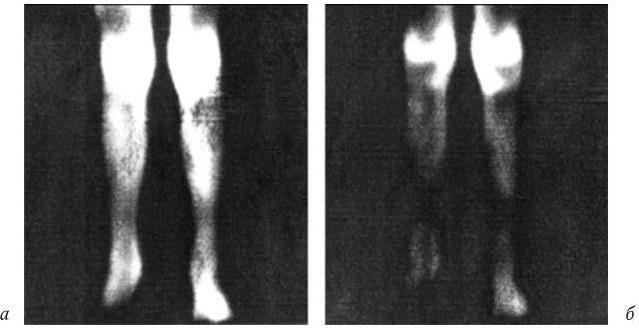

На рентгенограмме с прямым многократным увеличением отчетливо виден процесс резорбции костной ткани, образования эрозий, узур у больной с РА (рис. 13). На теплограмме воспаленного коленного сустава больной РА (рис. 14) представлено резко увеличенное тепловое излучение, вследствие увеличенного обмена паннуса. Оно буквально повторяет объем паннуса, который занимает всю суставную полость. Эта теплограмма артрита отчетливо отличается от теплоизлучения при реактивном синовите больных ОА с небольшими локальными очагами гипертермии (cм. рис. 12).

Рис. 14. Теплограмма нижних конечностей больной РА, 2-я степень активности

Выраженное диффузное теплоизлучение, с повышением температуры над суставом на 2,5 °C. Гипертермия буквально повторяет контуры воспаленной разросшейся синовиальной оболочки; а, б — сохранение гипертермии на разных режимах регистрации